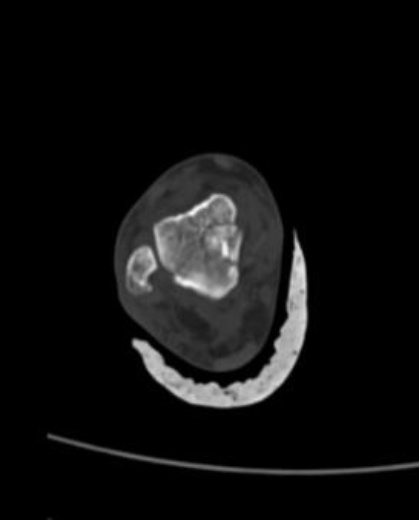

患者a,女性,56岁,主因“外伤致右踝肿痛畸形伴活动受限1小时”由急诊以“右距骨骨折伴距下关节脱位”收入院。查体:右踝内翻畸形,外观肿胀明显,压痛(+),纵轴叩击痛(+),可扪及明显骨擦感,足背动脉搏动可及,末梢血运及感觉良好。疼痛视觉模拟评分(Visual Analogue Scale, VAS) 8分,美国骨科足踝外科协会(American Orthopaedic Foot and Ankle Society, AOFAS)踝–后足评分0分。辅助检查:CT:右侧距骨骨折伴距下关节脱位。入院后完善检查,生命体征平稳,急行手法复位,具体操作步骤如下:患者取仰卧位,髋膝关节各屈曲45˚~60˚位,近端助手抱住小腿上端,远端助手两手分别握住足背和兜住足跟,用力牵引以纠正重叠移位。术者一手顶住外踝上方,另一手将足跟由外向内侧挤压(矫正内翻),同时适当外旋前足,听到“咔嗒”声提示关节复位,维持牵引下予石膏固定,复位后予消肿止痛治疗,嘱进行足趾功能锻炼。根据复位后影像检查所示,为防止骨折断端移位,与患者沟通病情后择期手术。手术记录如下:麻醉满意后取仰卧位,常规消毒铺单贴膜,术中取右足前内侧口长约1.5 cm,逐层切开皮肤、皮下组织和深筋膜,打开伸肌支持带,见右足距骨骨折,暴露断端,外侧子2根克氏针临时固定,C臂机透视下骨折断端复位情况可,子2枚加压中空心接骨螺钉固定,拔除克氏针。C臂机透视见骨折复位良好,生理盐水冲洗切口,逐层缝合,术程顺利,安返病房。术后予消肿止痛等对症治疗。

从影像学表现来推断其损伤机制:患肢旋前位,突然遭受内翻暴力,距骨体部内侧后方首当其冲,与跟骨暴力挤压,致该部粉碎性骨折,随之暴力传导,致距骨骨折伴脱位。图1可以看出骨折线是从距骨体部靠近距骨颈部由胫侧上方斜劈腓侧下方,将距骨暴力分为两大骨折块,并有不同程度的脱位旋转外翻。图2所示复位后距骨踝穴在位,骨折断端对位对线尚可,复位石膏固定后其影像学见距骨体部后方存在些许小碎骨片,且受伤时踝内翻畸形,腓侧皮肤张力大,故思考将石膏中立位改为踝外翻位更为合适。图3所示术后及术后3月复查,影像学表现示关节在位,骨折对位对线良好,未见其他明显异常。本例临床病例随访时间不足,无法评估患肢预后。

(a) (b) (c) (d)

Figure 1. Three-dimensional reconstruction of the patient’ bones at the time of injury

1. 患者受伤时的骨三维重建